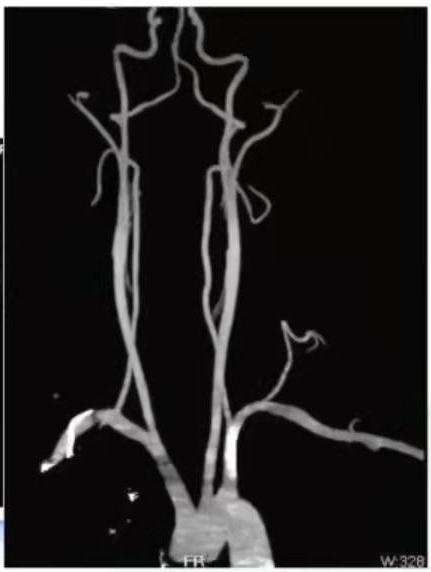

患者诉有咽颈痛,向左侧转头明显,治疗过程中请耳鼻喉科协助诊疗,并完善头颅CT三维重建,测量左侧茎突长度约36.6mm。

图9:头颅CT三维重建备注:图中的箭头所指为左侧茎突,红色圆圈所指为左侧茎突由这个病例,我们进一步了解一下茎突综合征。